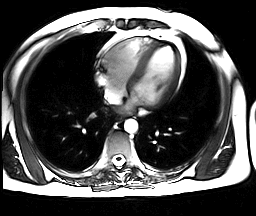

Магни́тно-резона́нсная томогра́фия (МРТ) — способ получения томографических медицинских изображений для исследования внутренних органов и тканей с использованием явления ядерного магнитного резонанса. Способ основан на измерении электромагнитного отклика атомных ядер, находящихся в сильном постоянном магнитном поле, в ответ на возбуждение их определённым сочетанием электромагнитных волн. В МРТ такими ядрами являются ядра атомов водорода, присутствующие в огромном количестве в человеческом теле в составе воды и других веществ[1].

Томография позволяет визуализировать с высоким качеством головной, спинной мозг и другие внутренние органы. Современные технологии МРТ делают возможным неинвазивно (без вмешательства) исследовать работу органов — измерять скорость кровотока, тока спинномозговой жидкости, определять уровень диффузии в тканях, видеть активацию коры головного мозга при функционировании органов, за которые отвечает данный участок коры (функциональная магнитно-резонансная томография — фМРТ).

Современные технологии и внедрение компьютерной техники обусловили возникновение такого метода, как виртуальная эндоскопия, который позволяет выполнить трёхмерное моделирование структур, визуализированных посредством КТ или МРТ. Данный метод является информативным при невозможности провести эндоскопическое исследование, например, при тяжёлой патологии сердечно-сосудистой и дыхательной систем. Метод виртуальной эндоскопии нашёл применение в ангиологии, онкологии, урологии и других областях медицины.